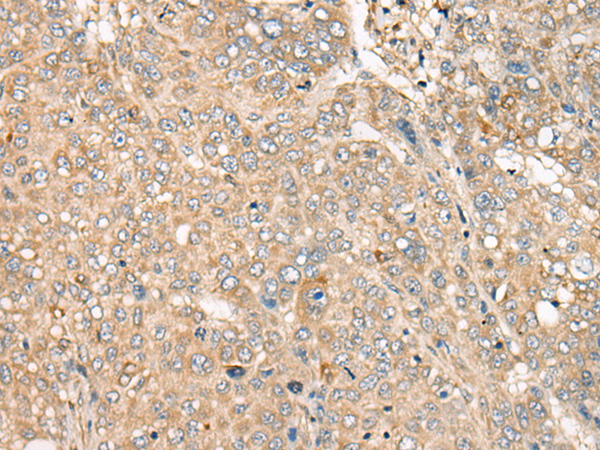

分类: 科研抗体货号: P09404别名: RESA1; SELRC1; C1orf163应用: WB,IHC反应种属: Human, Mouse